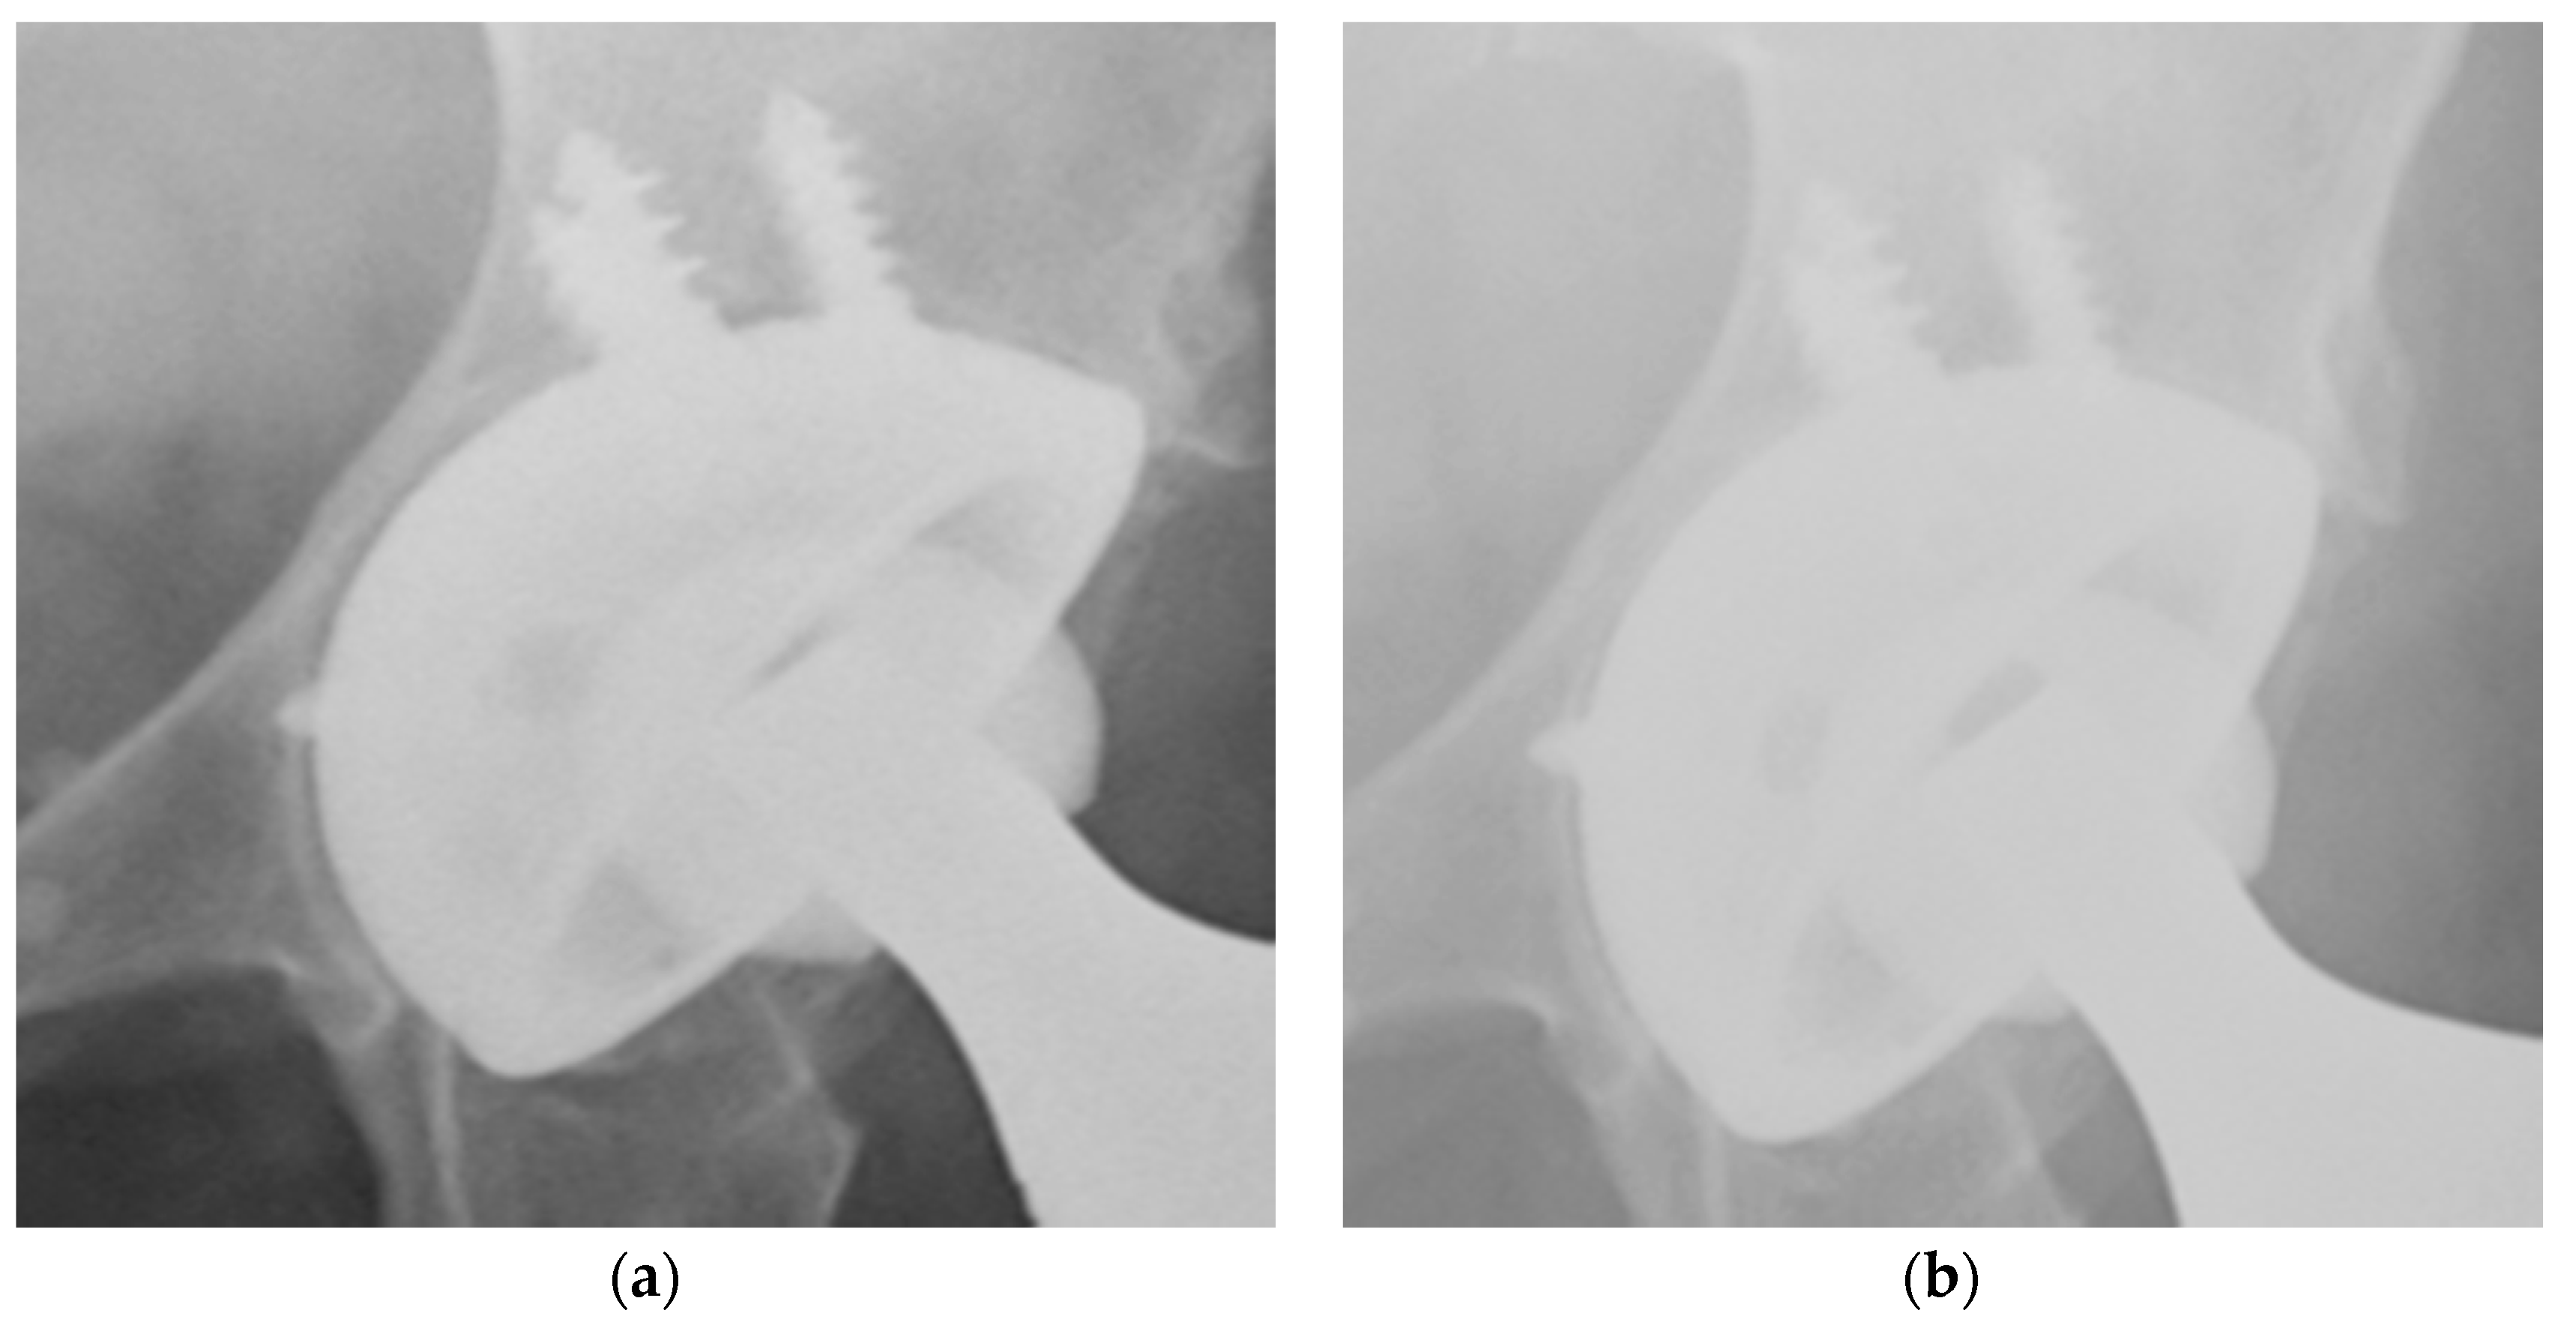

2. Materials and Methods

3. Results